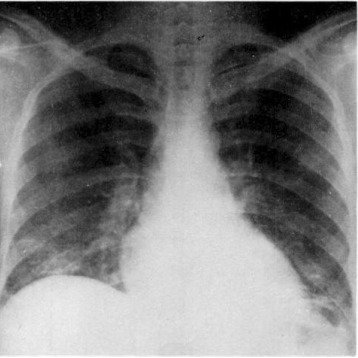

- Chest X-ray or lung function tests

- Chest imaging (X-ray or CT scan)

- Lung function tests and spirometry